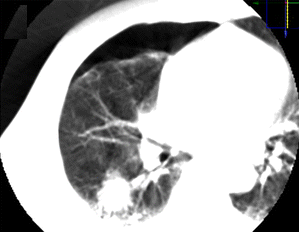

| 后入路下肺深部病变穿刺 | 通气肺实质内进针 |

![]() |

| 完成穿刺 | ABCS技术封长针道 |